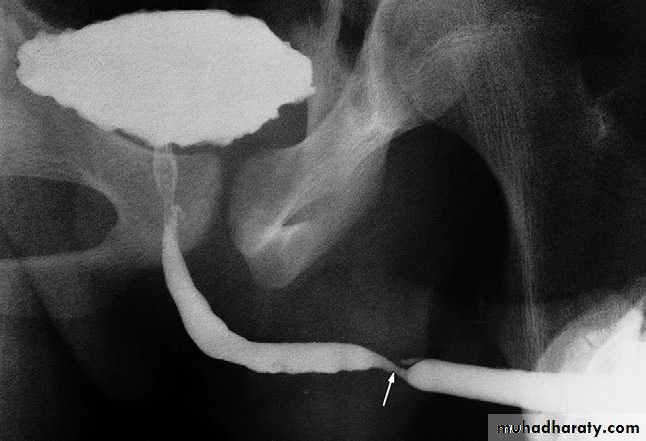

Urethrography

The urethra is visualized during voiding cystourethrography.For full visualization of the male urethra, however, an ascending urethrogram with contrast medium injection via the external urethral meatus is necessary .The usual indications for the examination are:

- The identificationof urethral strictures

- To demonstrate extravasation from

the urethra or bladder neck

following trauma.